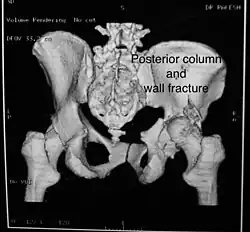

Posterior column As with posterior wall injury, this also typically occurs due to dash board injury. Posterior column + Posterior wall These fractures are extensions of elementary fractures. With the involvement of the posterior wall, the difficulty in treatment increases. These fractures are rarely amenable to non-surgical treatment. Due to posterior wall fracture, the hip is usually dislocated posteriorly, requiring immediate reduction of dislocation and surgical reconstruction after a few days.

The posterior column with posterior wall fracture occurs due to dashboard injury. The anteroposterior view may give clues to these injuries. Judet views and CT scans help in knowing the extent of the injury.

2. Iliac oblique view. This view shows the whole of the ilium, the posterior column, and the anterior wall

Iliac oblique view showing Posterior column and Anterior wall